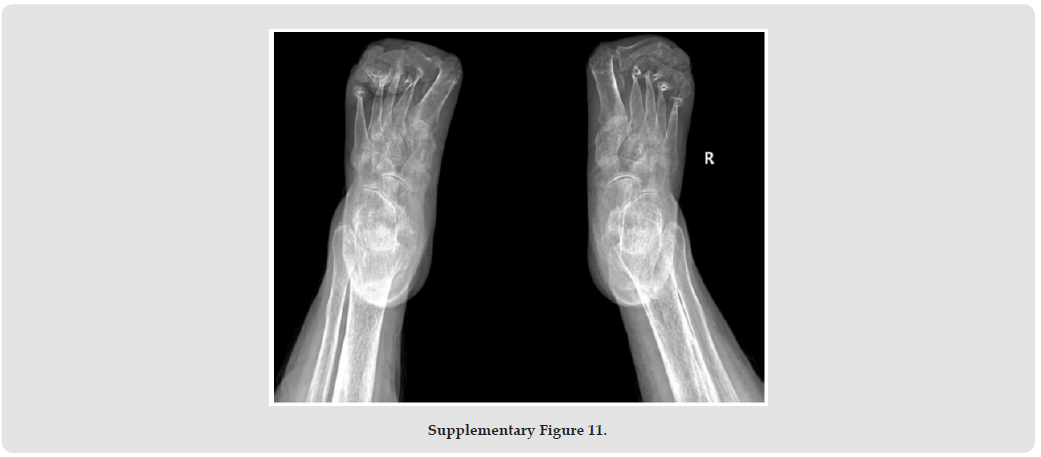

Psoriatic arthritis (PsA), a systemic autoimmune disease, manifests with remarkable clinical heterogeneity [1]. While axial involvement and peripheral joint destruction are well documented, the coexistence of severe spinal kyphosis and Mutilans-type arthropathy remains exceptionally rare. We present a diagnostically challenging case with concurrent progressive spinal deformity and osteolytic features of Mutilans [2]. This case report describes the complex clinical presentation of a rare psoriatic arthritis (PsA) patient with severe kyphosis and mutilating arthritis. A 69-year-old woman with a 50- year history of psoriasis developed worsening skin symptoms and joint pain in 2019. She was treated with cyclosporine, ezicizumab and secukinumab, which resulted in partial relief of skin symptoms but progressive joint destruction. Over the past two years, he had developed a complex sagittal and coronal spinal deformity (thoracolumbar kyphosis with scoliosis), accompanied by characteristic “telescopic” phalangolysis and ulnar deviation of the right hand. His serum markers (RF, anti-CCP, etc.) were normal. Imaging showed the coexistence of heterotopic ossification and osteolysis, consistent with the diagnosis of residual PsA combined with spinal PsA. The clinical significance of this case is that it highlights three key issues. Firstly, rapidly progressive spinal lesions can occur in the absence of a typical serological marker (negative HLA-B27); secondly, biological agents can cause separation of skin and joint effects.

Third, mechanical stress may accelerate the progression of spinal deformity in susceptible individuals. This suggests that dynamic monitoring of the spine in PsA patients should be intensified, especially in patients with long-term good skin control but new axial symptoms, and the evaluation strategy should be adjusted. Future research needs to further explore the mechanical-inflammatory interaction mechanism and establish precise treatment pathways for different clinical phenotypes. This case provides an important clinical demonstration to recognise the heterogeneity of PsA and the complexity of treatment (Supplementary Figures 1-11).